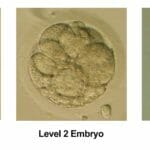

Cleavage Stage Embryo Grading